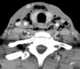

Neck infection